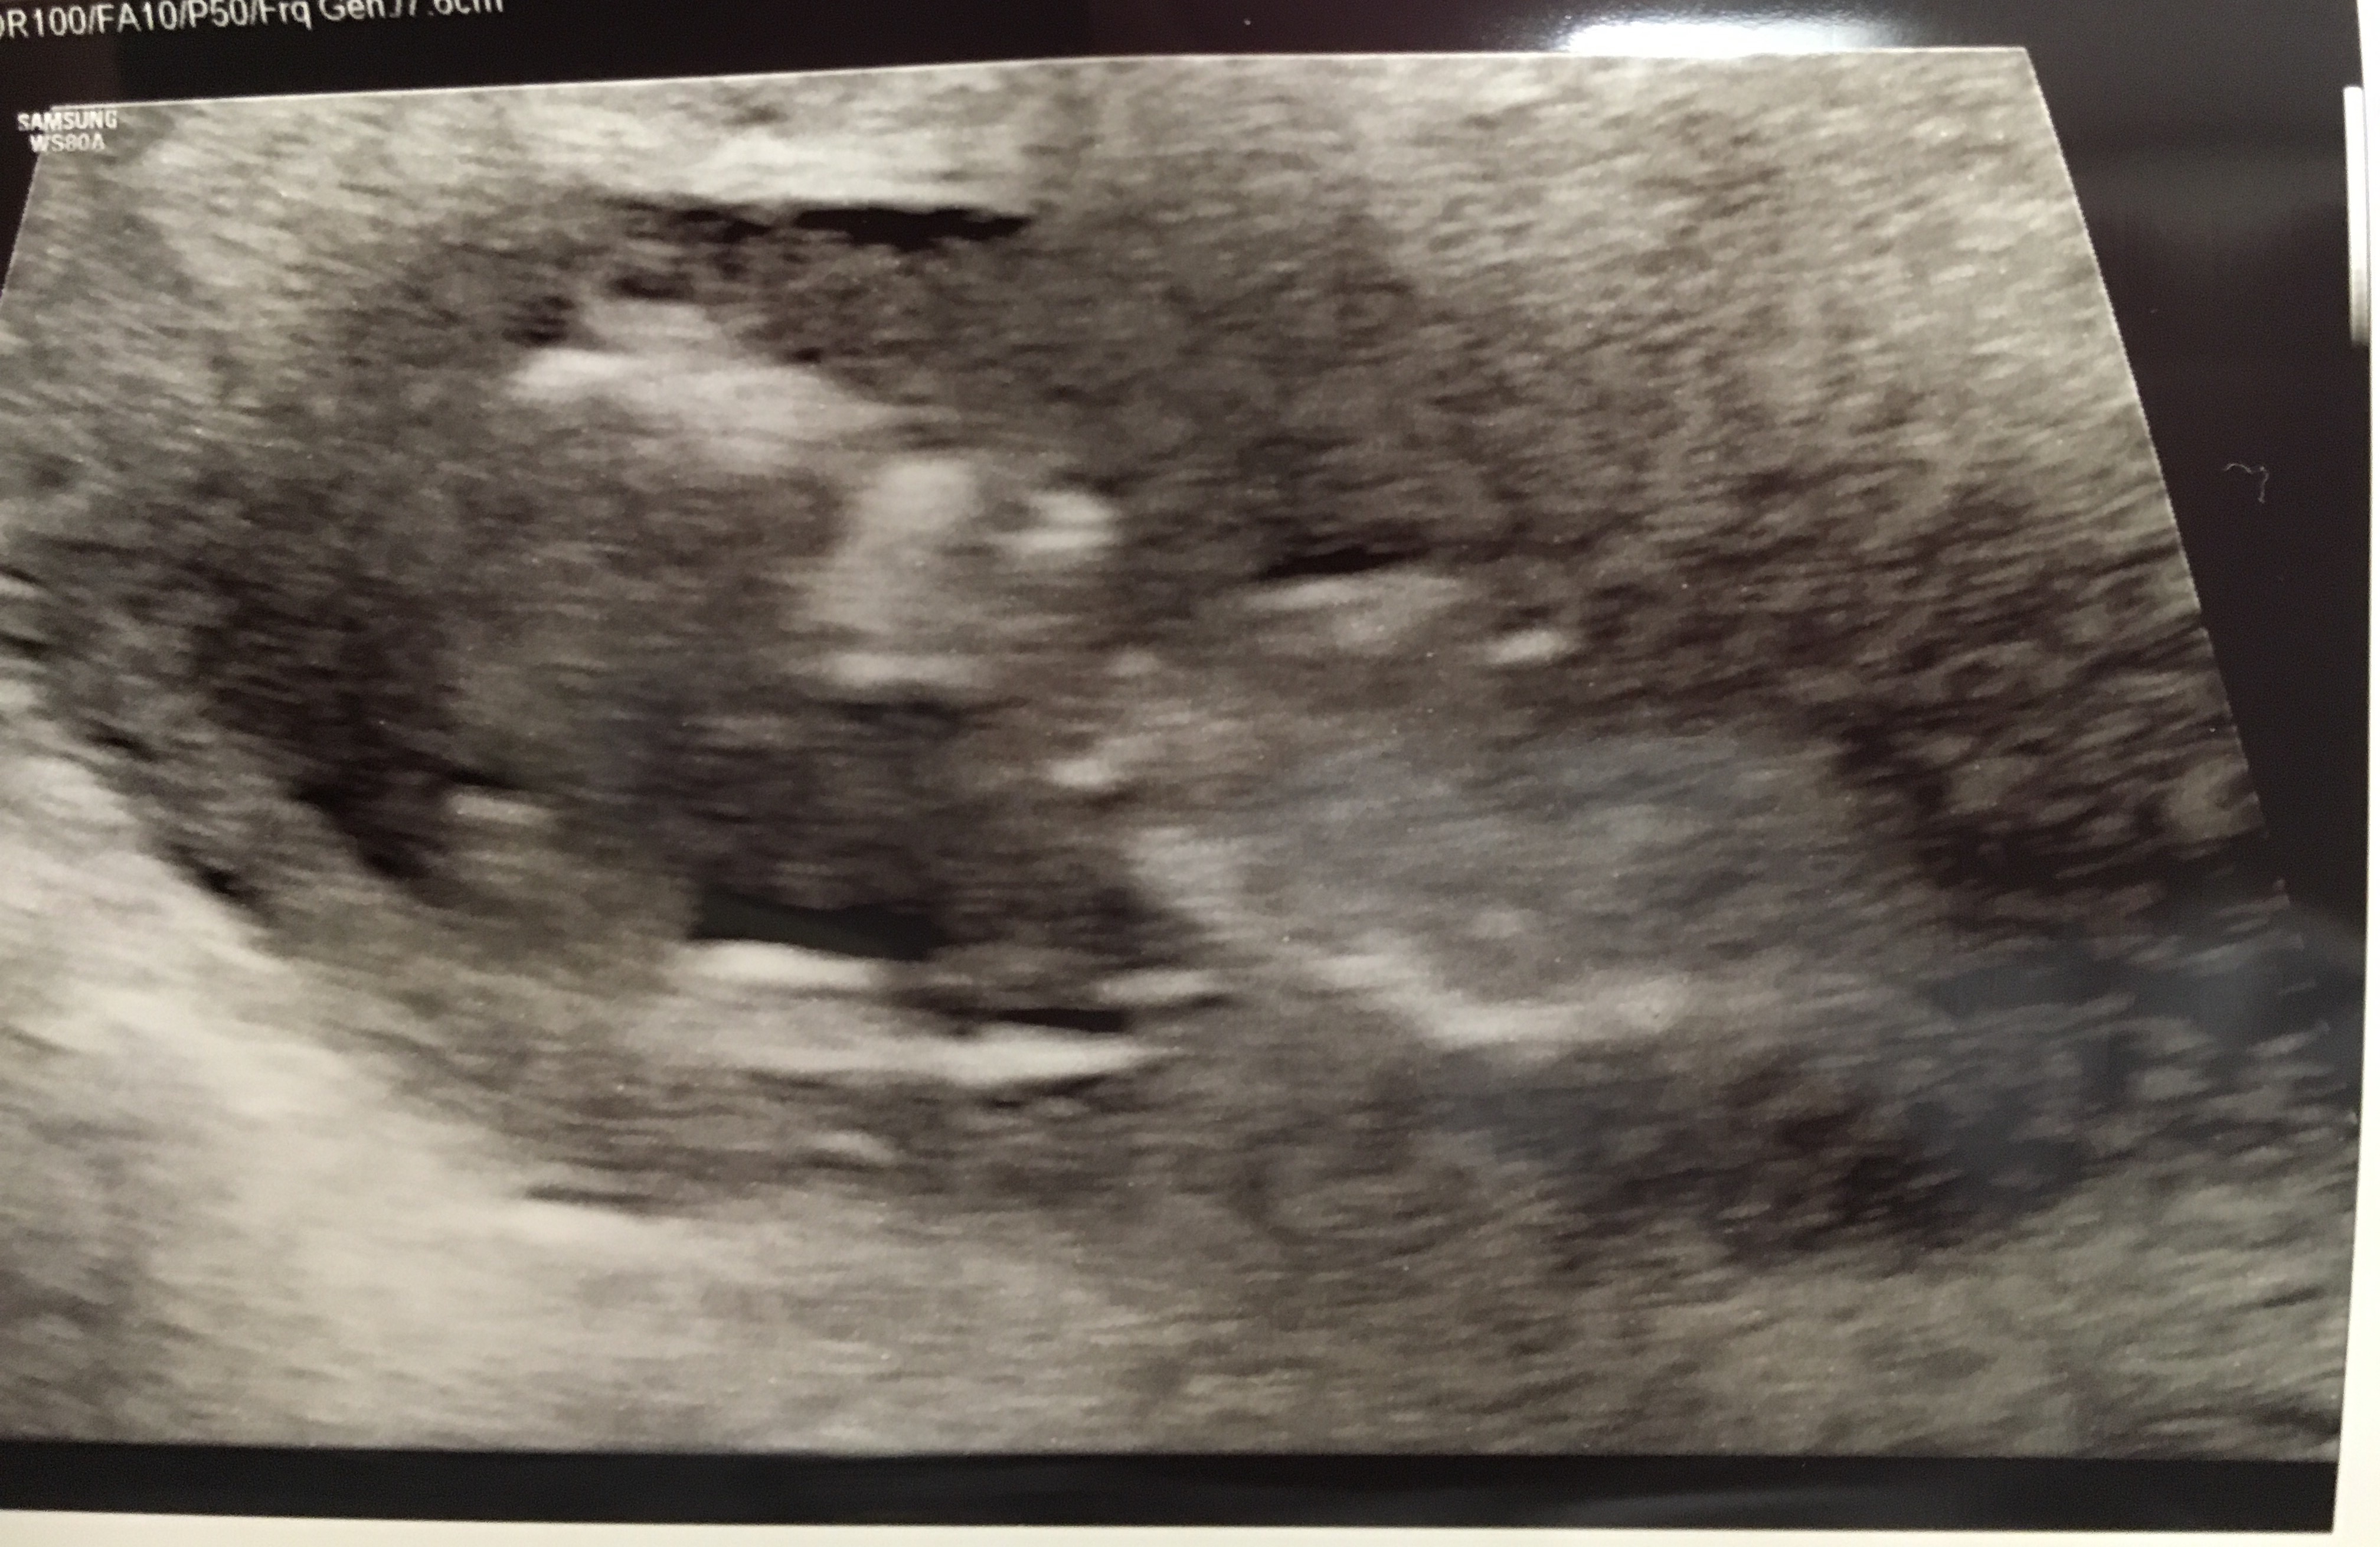

Our NT scan went well! They want the measurement to be below 3, and little miss was 1.3.

She kept dancing the whole scan. She never stopped. I’m actually already feeling her movements, and now I know why!

And, as promised…

Profile view 🙂

all the little fingers

laying with her hand above her head